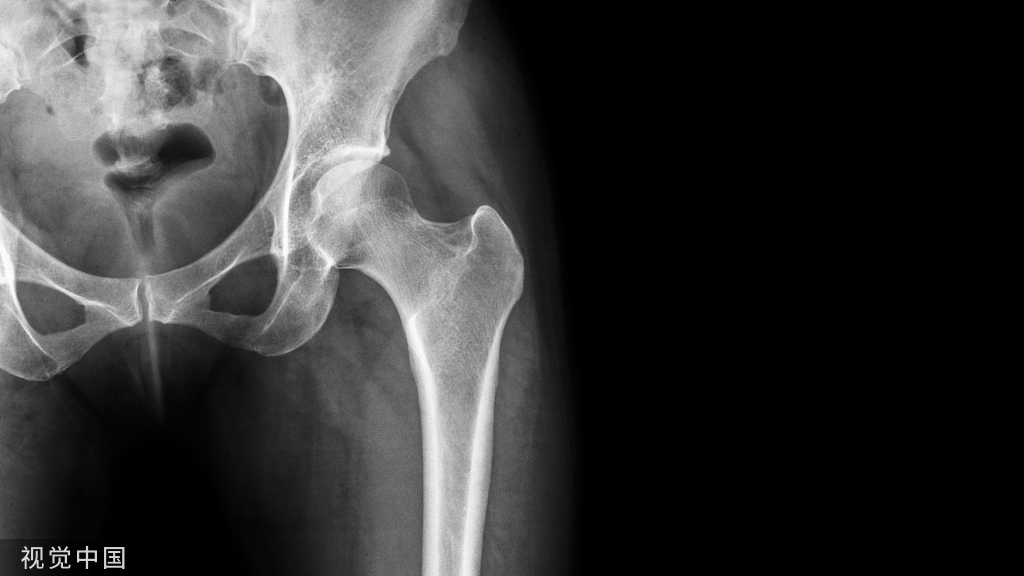

66岁女患者,因为膝关节疼痛到影像科检查,却偶然发现右侧股骨下端有类似“爆米花”样的异常信号。

看看下面的MRI、DR,你会做出怎样的诊断?

影像表现:平片、CT所见股骨下段髓腔内可见爆米花样高密度灶,边缘清楚。MRI示病灶T1呈低信号,T2呈不均匀高信号,符合软骨小叶信号。

诊断意见:考虑右股骨内生软骨瘤。